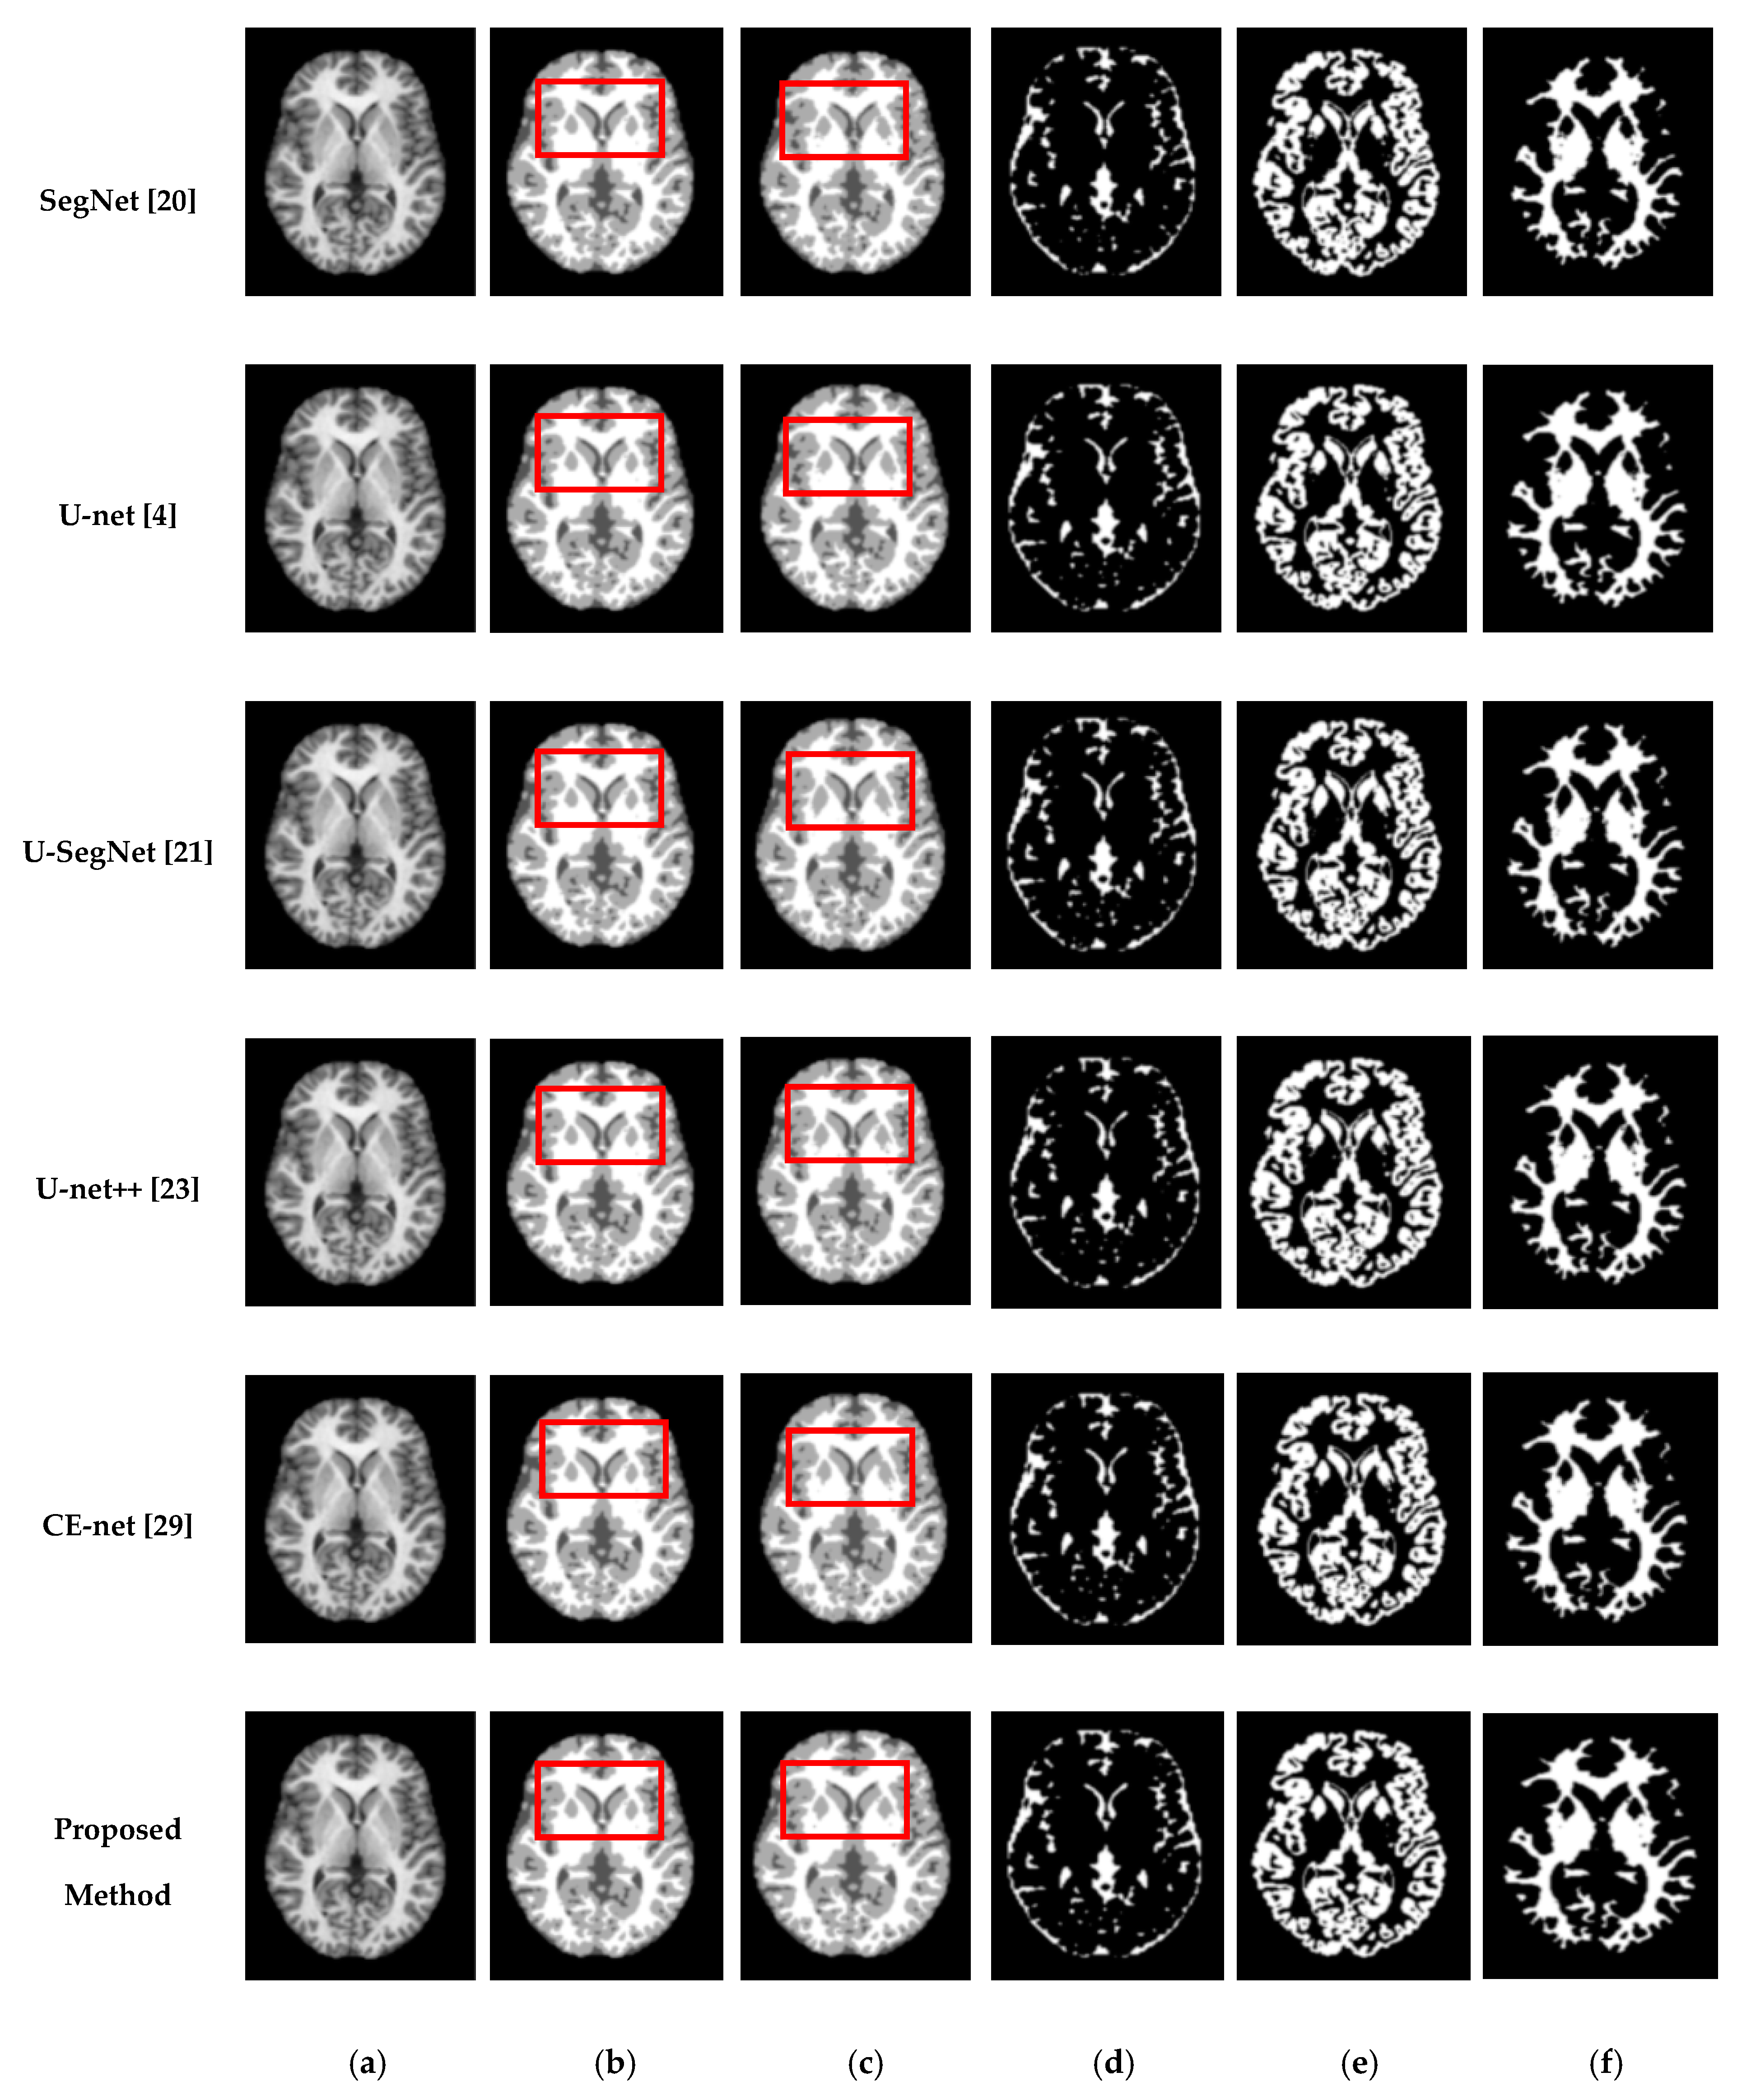

We also assessed the segmentation performance in terms of the mean square error (MSE), which is the average square difference between the original and predicted Y values. The Hausdorff distance (HD) [] was used to determine the dissimilarity between two sets in a metric space. The two sets of small Hausdorff distances are almost identical. HD and MSE are computed as listed in Table 2, where D is the Euclidean distance between two pixels, and R and C are the image height and width, respectively. To compare the segmentation results of various network architectures, we experimented on SegNet, U-net, U-SegNet, U-net++, and CE-net models under the same experimental conditions. Figure 7 and Figure 8 show comparisons of the segmentation results. As shown in Figure 7 and Figure 8, the proposed method shows superior results in terms of the quality of the segmentation map compared to those of other conventional methods. Although the skip connections in the U-net improve feature representations by combining low-level and high-level information, they suffer from a large semantic gap between low- and high-resolution feature maps, resulting in high misclassification rates of brain tissues. Furthermore, for medical images with low contrast, blurred boundaries between different tissues, the segmentation accuracies of U-net and SegNet are significantly degraded. Because the network layers in U-net++ are connected through a series of nested, dense skip pathways, leading to redundant learning of features, they did not show good performance. In particular, it can be observed that there are misclassification results in the feature maps generated by SegNet, U-net, and U-net++ in the red boxes of Figure 7c and Figure 8c. Although U-SegNet with pooling indices and skip connections yields better segmentation results, it fails to capture fine details, as shown in Figure 8c. From the highlighted red boxes in Figure 8, it can be observed that U-SegNet fails to identify differences between WM and GM tissues, and most of the GM tissues are incorrectly predicted as WM. The CE-net extracts multi-scale information through a context encoder block for the segmentation of medical images. However, the context encoder block is employed only at the bottleneck layer of the model, and thus this multi-scale information could be irrelevant by the time it reaches the final decoder layer for classification. To overcome these limitations, we extract multi-scale information at each network layer followed by the GAM to enhance the segmentation performance by directing attention to related areas. This improved segmentation can be observed in the results obtained using the proposed method. Similar results were observed for the segmentations obtained from the IBSR images, as shown in Figure 8. It can be observed that the proposed network obtains finer details than the other architectures. These results indicate that our proposed approach can strongly recover finer segmentation details while bypassing distractions between tissue boundary regions.

Figure 8.

Segmentation results for GM, CSF, and WM from brain MRI image using the existing methods and the proposed method on IBSR dataset: (a) original input image; (b) ground-truth segmentation map; (c) their segmentation results obtained SegNet, U-net, U-SegNet, U-net++,CE-net, and the proposed method (top to bottom); (d) CSF maps obtained by SegNet, U-net, U-SegNet, U-net++,CE-net, and the proposed method (top to bottom); (e) GM maps obtained by SegNet, U-net, U-SegNet, U-net++,CE-net, and the proposed method (top to bottom); (f) WM maps obtained by SegNet, U-net, U-SegNet, U-net++,CE-net, and the proposed method (top to bottom).